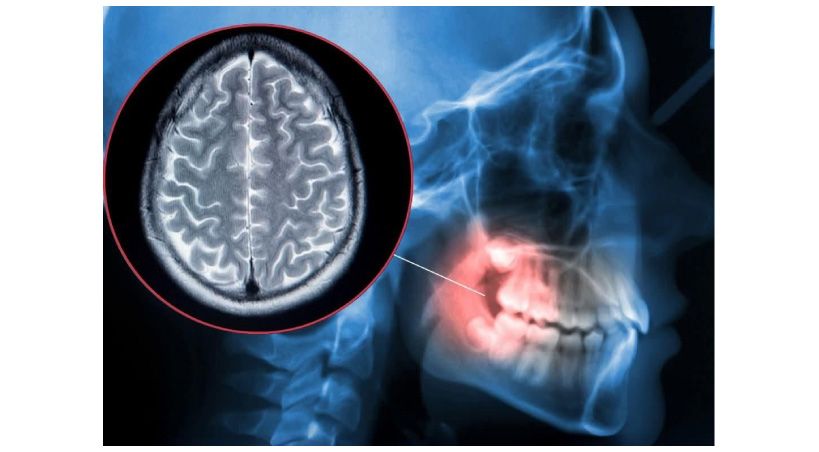

Asociación entre enfermedades periodontales y enfermedades cardiovasculares, diabetes y enfermedades respiratorias: Informe de consenso del Taller Conjunto de la Federación Europea de Periodoncia (EFP) y el brazo europeo de la Organización Mundial de Médicos de Familia (WONCA Europa)

• Existe una asociación independiente entre la periodontitis y las condiciones médicas, como las enfermedades cardiovasculares y la diabetes. Este informe es de un taller enfocado que reunió a expertos médicos y dentales y tuvo como objetivo crear vías colaborativas para la detección temprana de periodontitis y enfermedades no transmisibles.

La periodontitis se ha asociado con una variedad de enfermedades sistémicas, incluida la diabetes, enfermedades cardiovasculares y enfermedades respiratorias. También se asocia de forma independiente con la muerte prematura por todas las causas o por ECV, en particular en poblaciones multimórbidas, donde el impacto de la periodontitis es equivalente a tener diabetes mellitus comórbida. La periodontitis también da lugar a un aumento de los gastos médicos.

La periodontitis se asocia de forma independiente con enfermedades cardiovasculares, diabetes, enfermedad pulmonar obstructiva crónica (EPOC), apnea obstructiva del sueño y complicaciones de la COVID-19.